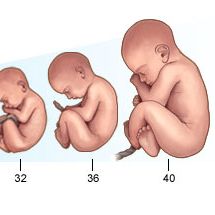

Várandósgondozás hétről-hétre